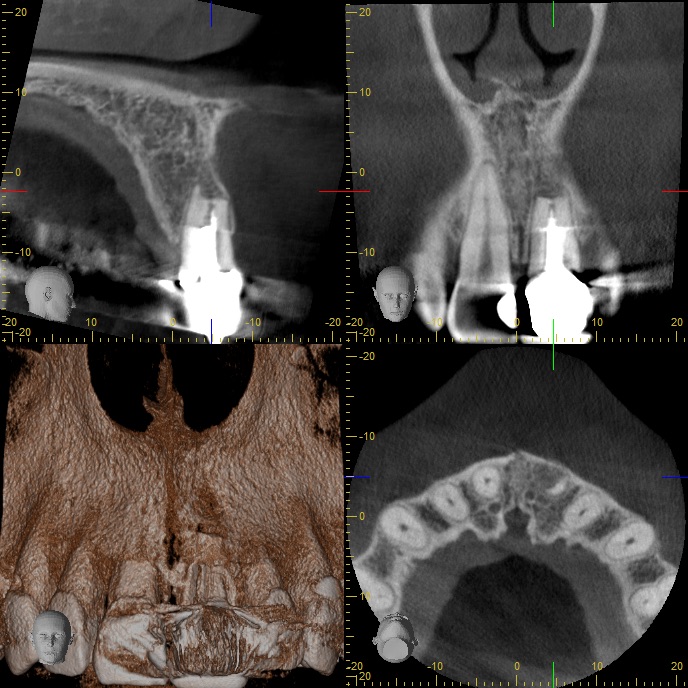

Abb3 Veröffentlicht 26. Juli 2016 am 688 × 688 in Röntgenlogisch erkennbare Verdachtsdiagnosen (2) Abb3